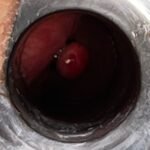

LASER LIAS FOR ANAL FISSURES AND BANDING OF HEMORRHOIDS